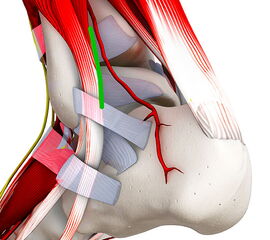

• Dokumentation der Durchblutung des Fußes (Pulse der A. tibialis posterior und der A. dorsalis pedis, ggf. Dopplersonographie, Rekapillarisierungzeit).

• Dokumentation der Sensibilität (Spitz/Stumpf Unterscheidung, 2 Punkte- Diskriminierung)